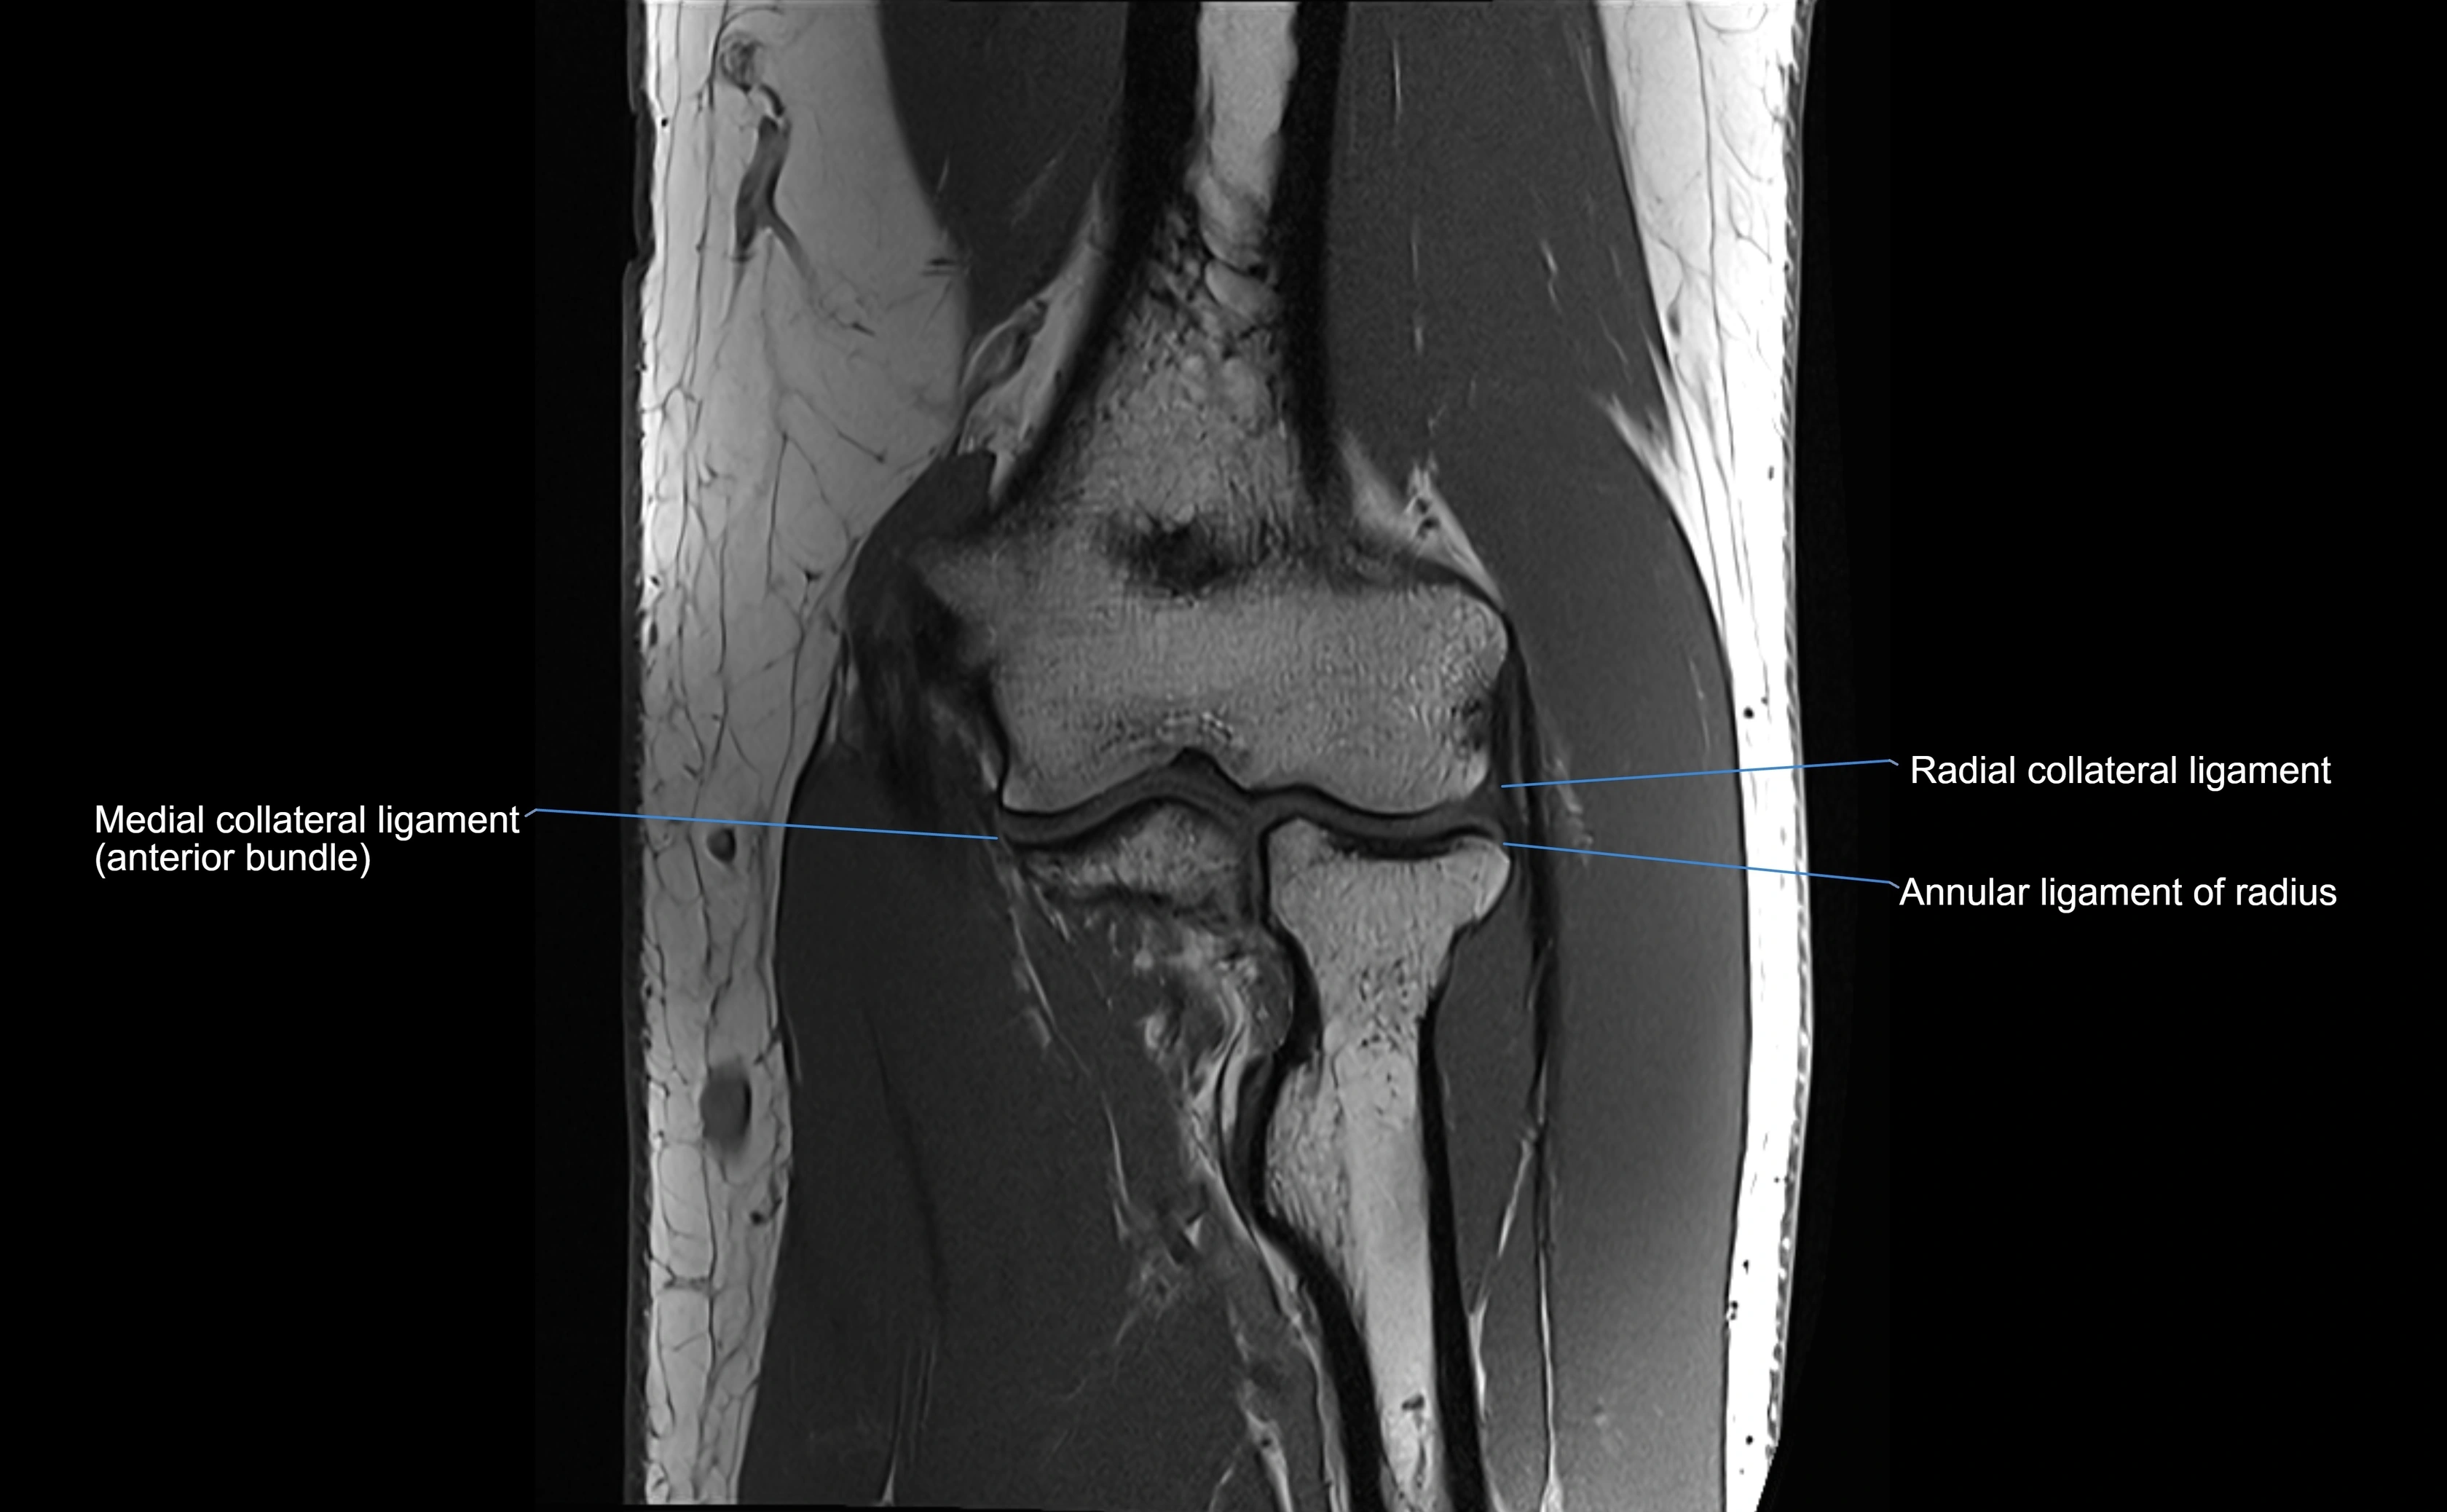

Annular ligament of radius

The annular ligament of the radius is a strong, circular band of fibers that encircles the head and neck of the radius, holding it securely against the radial notch of the ulna. It forms part of the proximal radioulnar joint, permitting smooth rotation of the radius during pronation and supination of the forearm.

The ligament acts like a collar or loop, maintaining radial head stability while allowing rotation. It is essential for forearm motion, elbow stability, and load transmission from the radius to the ulna and humerus.

Origin, Course, and Insertion

• Origin: Arises from the anterior margin of the radial notch of the ulna.

• Course: Forms a strong circular band that wraps around the radial head and neck, maintaining them within the radial notch.

• Insertion: Attaches to the posterior margin of the radial notch, completing a fibrous ring around the radial head.

• The inner surface of the ligament is lined with synovial membrane, allowing frictionless rotation.

MRI Appearance

T1-weighted images:

• Ligament: low signal intensity (dark), appearing as a continuous band around the radial head.

• Adjacent fat and marrow: bright, creating contrast with the ligament.

• Thickening or disruption indicates injury or fibrosis.

• Joint capsule and synovium seen as thin low-signal lines contiguous with ligament margins.